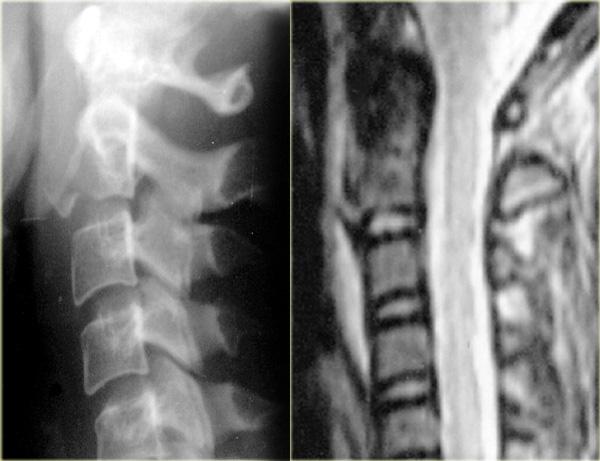

Bên trái là hình ảnh của một phụ nữ 44 tuổi bị ngã trên băng.

Sau đó bà bị ngã lần thứ hai vào sáng hôm sau, và sau đó mất hoàn toàn vận động và cảm giác.

Khám thực thể cho thấy liệt hai chi dưới kèm yếu nhẹ chi trên bên phải.

Ban đầu được đề xuất chẩn đoán tổn thương tủy trung tâm.

X-quang bình thường.

Các dấu hiệu bao gồm:

- Các mảnh xương nhỏ tách ra từ mặt khớp trên và dưới

- Khoang gian gai rộng ra tại C5-6

- Sưng nề mô mềm ở mức này về phía sau

- Hẹp nhẹ khoang đĩa đệm tại mức C5-6.

Các dấu hiệu CT này rất tinh tế và dường như không tương xứng với vấn đề thần kinh.

Trong trường hợp như vậy, MRI là bước tiếp theo cần thực hiện.

Đầu tiên chúng tôi trình bày hình CT mặt phẳng coronal và axial với cửa sổ mô mềm.

Có vật liệu tăng tỷ trọng ở phía sau khoang đĩa đệm, rất gợi ý thoát vị đĩa đệm do chấn thương.

Tụ máu ngoài màng cứng cần được đưa vào chẩn đoán phân biệt, nhưng dấu hiệu này chỉ giới hạn ở vùng khoang đĩa đệm, khác với hình ảnh của khối máu tụ.

Tiếp tục với hình MRI.